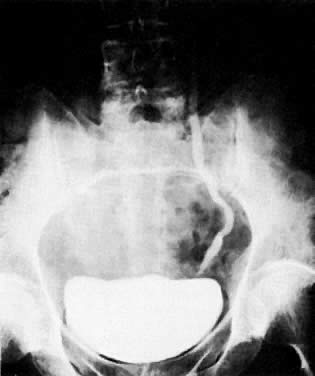

Previously, EU and retrograde pyelography have been the principal radiologic methods for examination of the urinary tract. As the tumor encases the ureter, a narrowed segment occurs (Fig. 36). The renal pelvis and calices and the ureter proximal to the involved area dilate (Fig. 37). With further involvement, the kidney ceases to function. Patients who have had a radical hysterectomy frequently have proximal ureterectasis to just below the pelvic brim. This radiologic finding lasts 6 to 12 months, and findings then gradually return to normal. The normal or narrowed distal ureters also are pulled medially secondary to the surgical procedure.

Fig. 36. Blocking ureterogram shows narrowed area in left distal ureter ( between arrows) in a patient wtih endometrial carcinoma.

Fig. 37. Excretory urogram shows dilated right collecting system to the ureterovesical junction in a patient with cervical carcinoma.